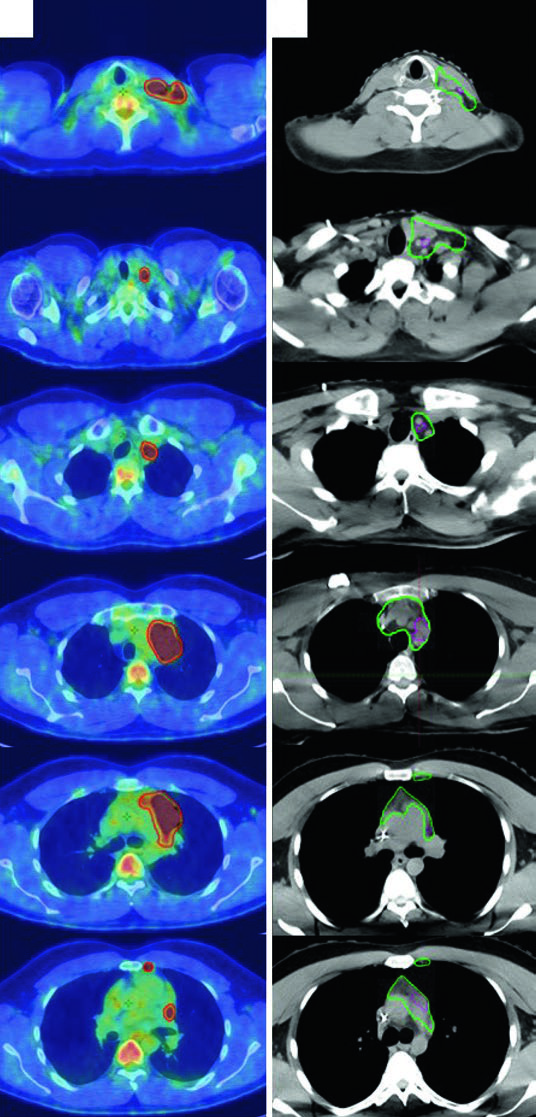

O caso clássico é um homem de 27 anos com LH esclerose nodular estádio IIA, não bulky, risco favorável, envolvendo regiões supraclavicular esquerda e mediastinal. Após 2 ciclos de ABVD, o PET pós-quimioterapia mostrou resposta metabólica completa (Deauville 2). Seguindo os critérios do H10 (German Hodgkin Study Group), foi tratado com 20 Gy de RT.

Para o delineamento, o PET/CT pré-quimioterapia foi registrado com a CT de simulação. A mudança no posicionamento dos braços, pescoço hiperestendido e máscara de 5 pontos retraindo os ombros gera diferenças anatômicas entre os exames — e exatamente essa incerteza justifica a abordagem ISRT. O paciente usou técnica de breath-hold, então não há expansão do CTV para ITV.

LH Avançado com Doença Bulky

Uma mulher de 31 anos com LH esclerose nodular estádio IIB bulky envolvendo linfonodos cervicais, supraclaviculares, mediastinais e hilares bilaterais recebeu 2 ciclos de ABVD (resposta completa no PET interim, Deauville 2), seguidos de 4 ciclos de AVD (Bleomicina descontinuada por toxicidade pulmonar). A RT consolidativa foi indicada pela doença bulky inicial.

O ITV final foi obtido por 4D-CT na simulação, contabilizando variações anatômicas respiratórias. A prescrição foi feita ao ITV mais a margem de PTV institucional. Esse caso demonstra como a ISRT adapta-se à anatomia pós-quimioterapia: o CTV respeita a extensão craniocaudal do GTV pré-quimio enquanto limita a exposição radial das estruturas normais adjacentes.